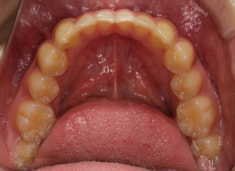

治療前